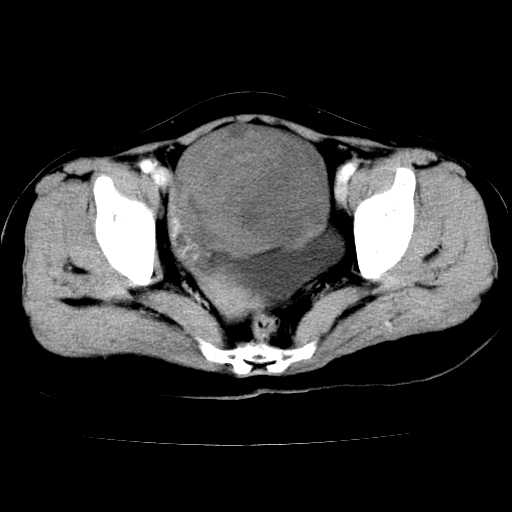

标题: CT24785:女,62岁,发现下腹部肿物半年。 [打印本页]

女,62岁,发现下腹部肿物半年,下腹部不适。

卵巢囊腺瘤或囊腺癌,建议免疫组化实验

卵巢囊腺瘤或囊腺癌可能。

考虑卵巢囊腺瘤或囊腺癌可能。